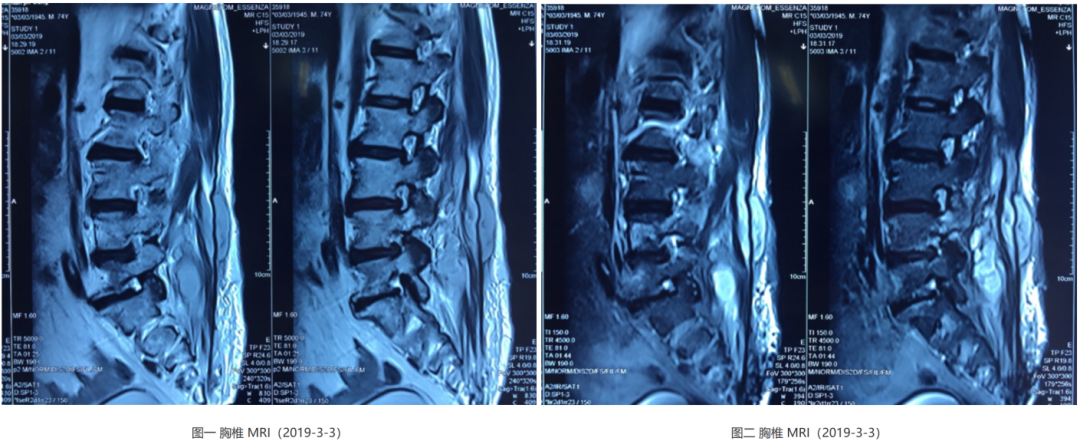

腰椎MRI检查提示「腰1-3水平椎管内及腰骶部,双侧腰大肌、竖脊肌内多发异常强化」,胸部CT提示左上肺类圆形厚壁空洞影,偏心性空洞。

可以看到腰椎有明显的肌肉间隙的脓肿形成,而且对于有局部椎骨有一定的破坏。